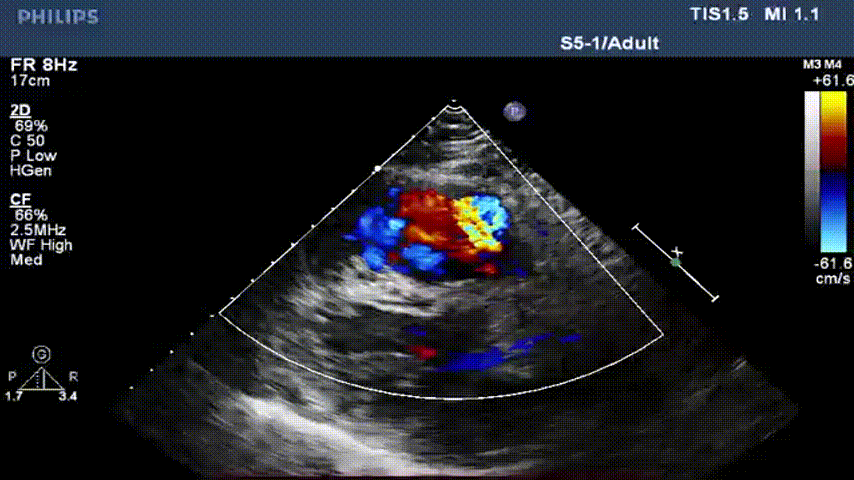

术后即可超声显示肺动脉瓣反流消失、瓣叶开闭正常

术后24小时超声显示瓣叶启闭功能正常